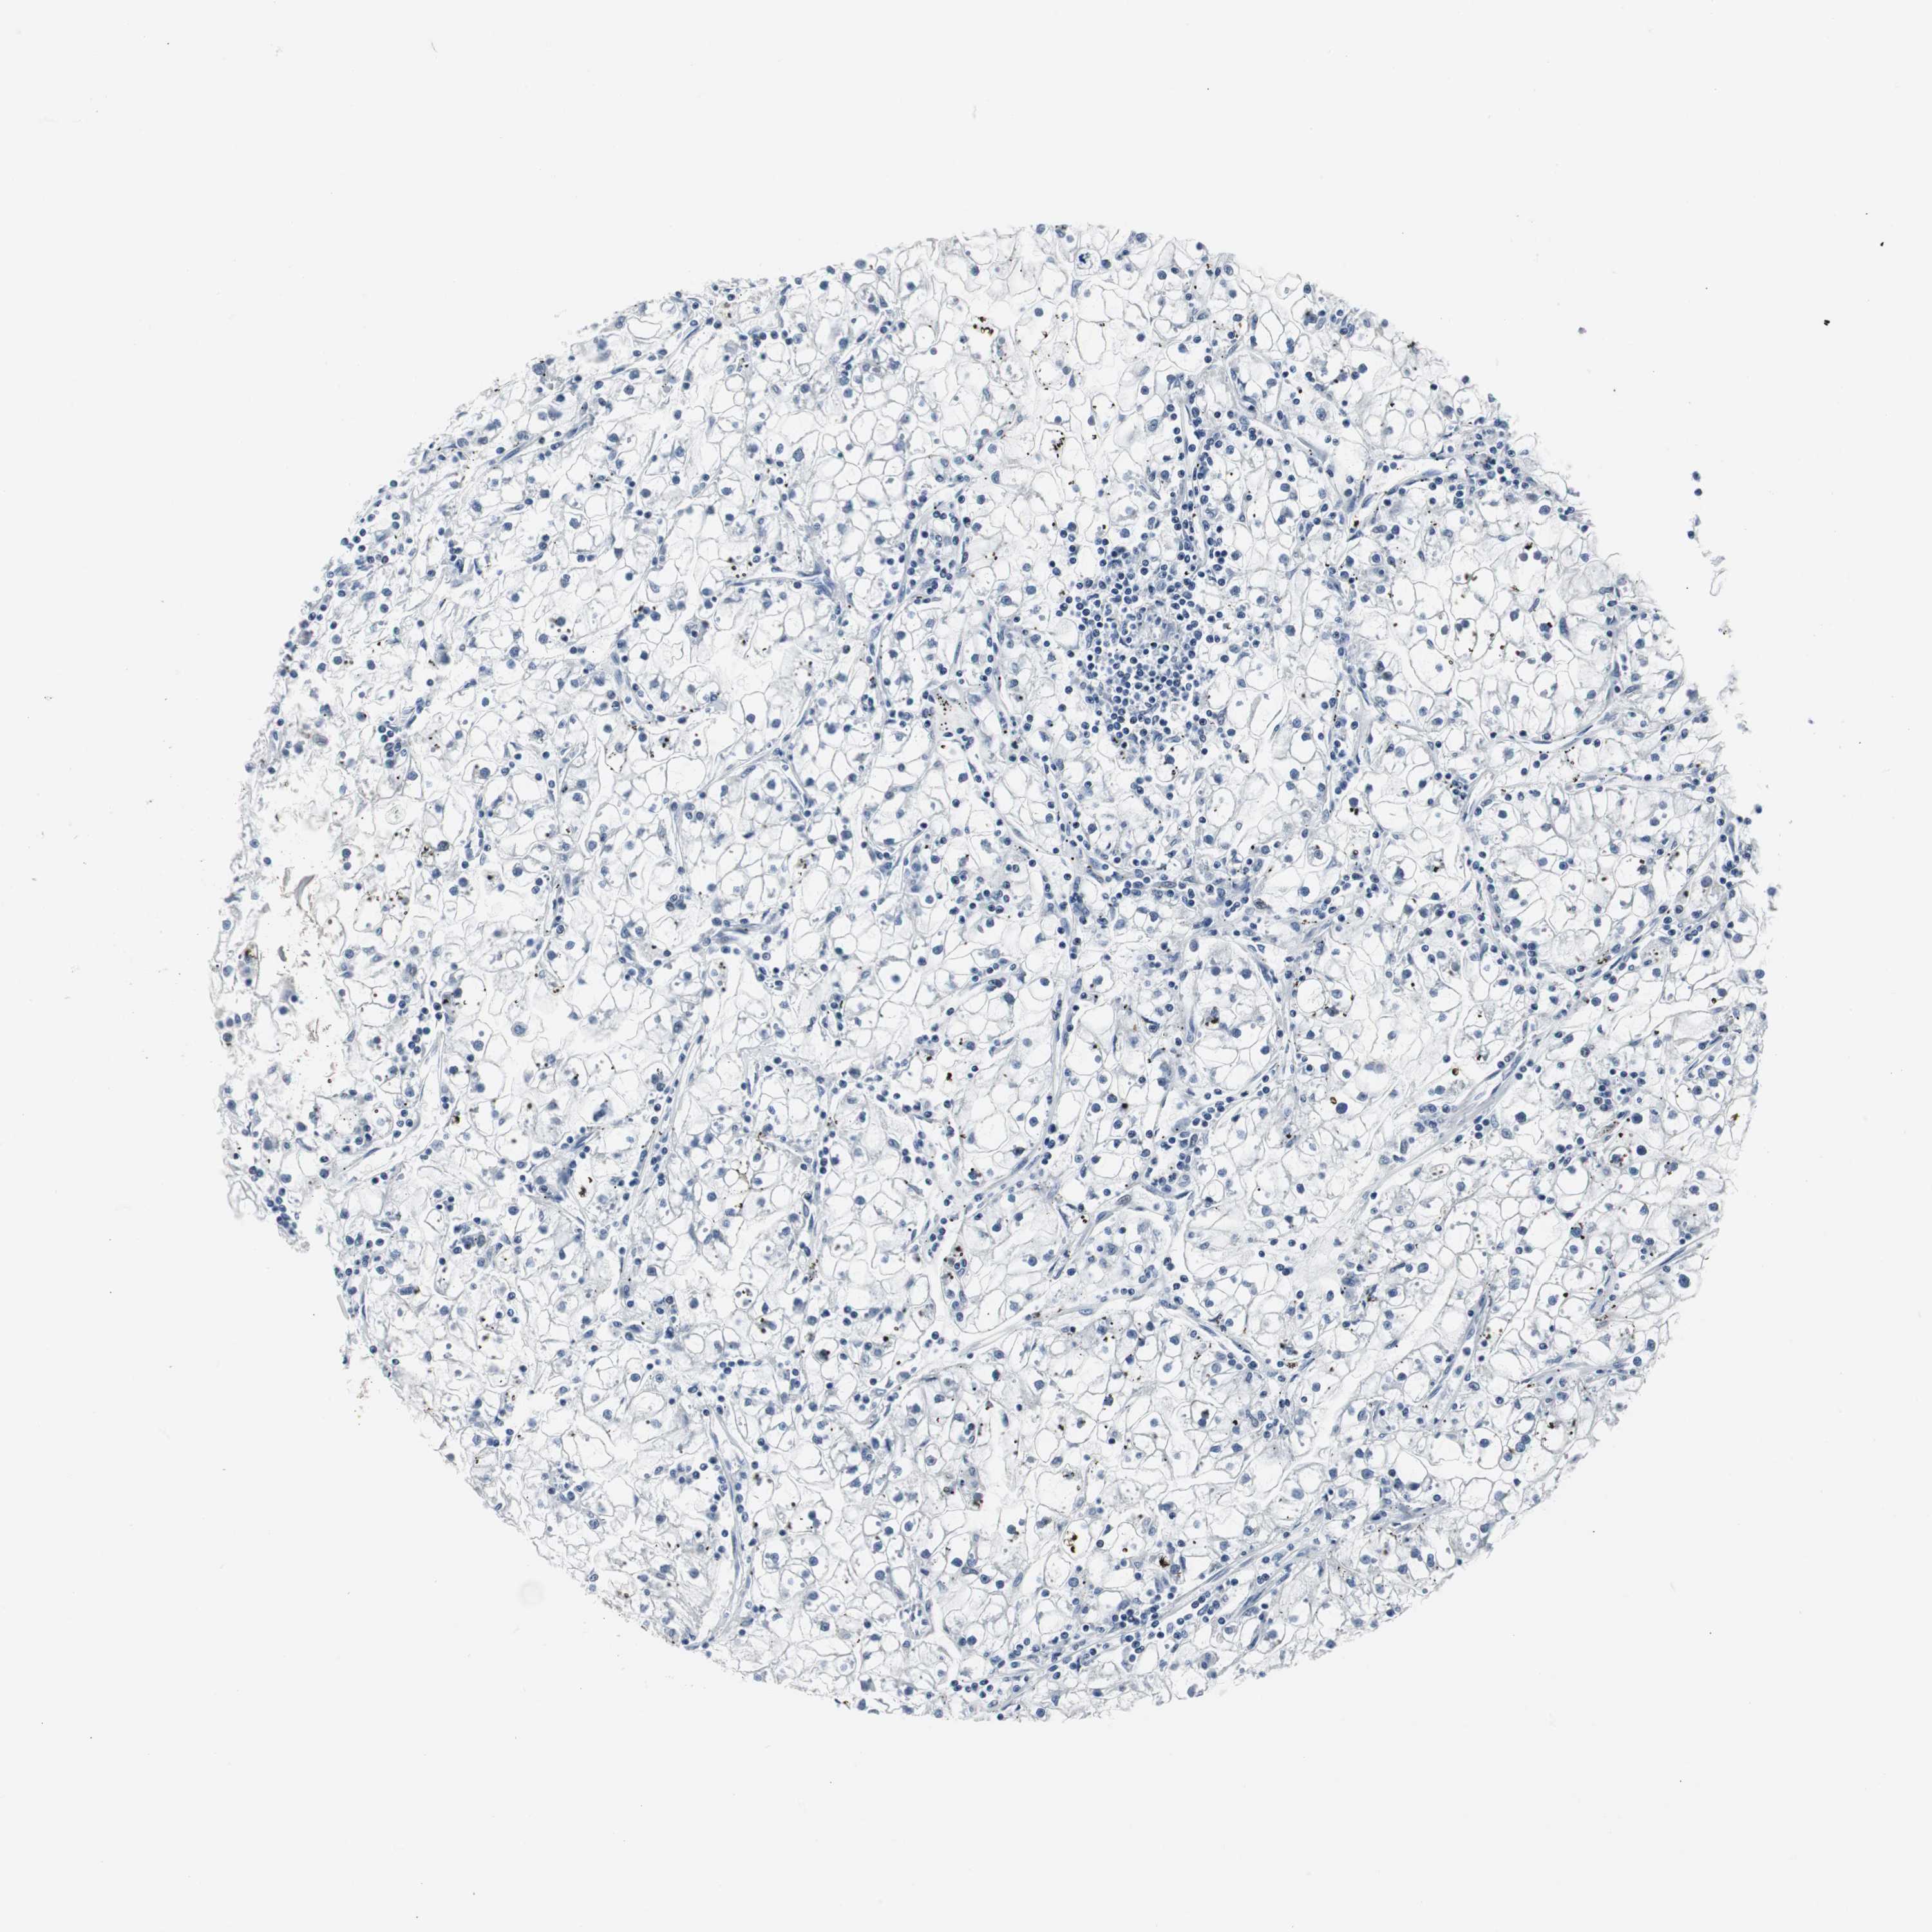

KIDNEY RENAL CLEAR CELL CARCINOMA (VALIDATION) - Interactive survival scatter ploti

The Survival Scatter plot shows the clinical status (i.e. dead or alive) for all individuals in the patient cohort, based on the same data that underlies the corresponding Kaplan-Meier plots. Patients that are alive at last time for follow-up are shown in blue and patients who have died during the study are shown in red.

The x-axis shows the expression levels (FPKM) of the investigated gene in the tumor tissue at the time of diagnosis. The y-axis shows the follow-up time after diagnosis (years). Both axes are complimented with kernel density curves demonstrating the data density over the axes. The top density plot shows the expression levels (FPKM) distribution among dead (red) and alive patients (blue). The right density plot shows the data density of the survived years of dead patients with high and low expression levels respectively, stratified using the cutoff indicated by the vertical dashed line through the Survival Scatter plot. This cutoff is automatically defined based on the FPKM cutoff that minimizes the p-score. The cutoff can be changed by dragging the vertical line or by entering a cutoff value in the square labeled "Current cut-off".

Under the Survival Scatter plot the p-score landscape (black curve; left axis) is shown together with dead median separation (red curve; right axis). Dead median separation is the difference in median mRNA expression between patients who have died with high and low expression, respectively. It is calculated as follows: median FPKM expression of dead patients with high expression - median FPKM expression of dead patients with low expression. This is intended to aid the user in visually exploring custom cutoffs and the associated p-scores and dead median separation.

Individual patient data is displayed and can be filtered by clicking on one or more of the category buttons on the top of the page. Categories describing expression level and patient information include: high, low, alive, dead, female, male and tumor stages. The scale of the x-axis can be toggled between linear and log-scale by clicking on the "x log" button. Mouse-over function shows TCGA ID, patient information and mRNA expression (FPKM) for each patient.

& Survival analysisi

Kaplan-Meier plots summarize results from analysis of correlation between mRNA expression level and patient survival. Patients were divided based on level of expression into one of the two groups "low" (under cut off) or "high" (over cut off). X-axis shows time for survival (years) and y-axis shows the probability of survival, where 1.0 corresponds to 100 percent.

DOK1 is not prognostic in Kidney Renal Clear Cell Carcinoma (validation)

Best expression cut offi

: 12.87

Average pTPM 10.2

Number of samples 100